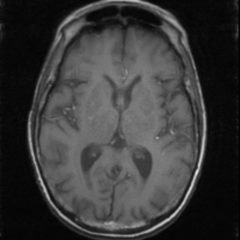

A 38-year-old female with body mass index (BMI) of 47.3 and history of insulin-dependent diabetes mellitus presented to the emergency department with headache. She described the headache as slowly progressive over three weeks with “pressure-like” quality and 9/10 severity at the back of her head with associated blurred vision. Physical exam revealed normal vital signs, normal neurologic exam, intact visual fields, no nuchal rigidity, and a normal fundoscopic exam except for mild papilledema bilaterally.

Optic nerve sheath diameter (ONSD) was measured via ultrasound with diameter 5.7mm on left and 6.2mm on right. In order to measure ONSD via optic ultrasound the high-frequency linear array probe (7.5-10-MHz or higher) is utilized in B-mode. The patient is positioned supine and an occlusive dressing, such as Tegaderm, is placed over a closed eyelid with copious conductive gel on top of the dressing. Being careful not to put pressure on the globe, an axial cross-sectional image of the globe is obtained. As demonstrated in the image “annotated left eye ONSD pre-lumbar puncture,” there are two main anechoic areas of the globe, the anterior chamber and the vitreous humor. These anechoic structures are separated by the hyperechoic iris, which surfaces the hyper-echoic-lined lens. At the back of the vitreous humor is the retina, which leads posteriorly into the optic nerve. The optic nerve is the hypoechoic structure posterior to the retina and surrounded by the hyperechoic subarachnoid space, which is encased by the hypoechoic dura mater. The outer edge of the hypoechoic dura matter is where the ONSD is measured.1 The user applies calipers to measure 3mm perpendicularly behind the retina along the hypoechoic optic nerve, and at this level the transverse dimensions of the ONSD are measured using calipers as shown in the images.

Computed tomography (CT) of the head was performed and showed no abnormalities. Lumbar puncture was performed in left lateral decubitus position revealing elevated opening pressure of 29cm H2O. Thirty-five mL of clear cerebral spinal fluid was drained and was negative for all infectious studies.  Optic nerve sheath diameter was again measured post-lumbar puncture with diameters 5.4mm on left and 5.4mm on right.